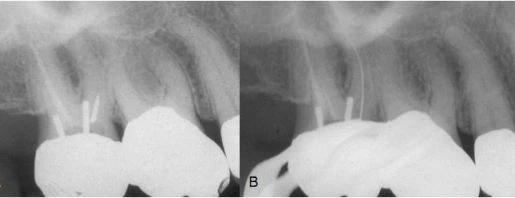

Hình 4. A, Đầu thăm dò nội nha gãy ở miệng ống tủy gần ngoài của răng cối lớn thứ hai hàm trên. B, Tháo mảnh gãy bằng một tay siêu âm.

Hình 4 minh họa cho trường hợp một đầu thăm dò nội nha gãy cản trở hoàn thành quá trình điều trị nội nha ở chân ngoài gần của răng cối lớn thứ nhất hàm trên. Việc điều trị được thực hiện 8 năm trước khi khởi phát triệu chứng trên lâm sàng. Kỹ thuật siêu âm được dùng để loại bỏ mảnh gãy và việc điều trị lại được hoàn tất.